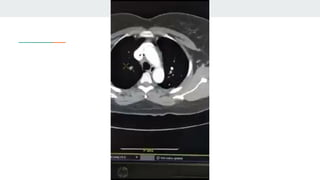

Os achados característicos de TEP agudo são

● 1) defeito de enchimento parcial central ou periférico circundado por um pequeno halo de contraste

2) completo defeito de enchimento com obliteração de todo o vaso avaliado.

Num evento de TEP agudo, as artérias pulmonares quando completamente obstruídas geralmente

têm diâmetro aumentado

1. Nos exames de pesquisa de TEP deve-se avaliar os achados vasculares e

parenquimatosos

2. A avaliação da janela de pulmão é importante não apenas para identificar as artérias

pulmonares devido sua proximidade com o brônquio, mas também para avaliar sinais

complementares que podem ser úteis em sugerir o diagnóstico de TEP.

3. Outros sinais tomográficos tais como áreas de atenuação reduzida e efusão pleural

são de pouca utilidade em distinguir pacientes com e sem TEP agudo